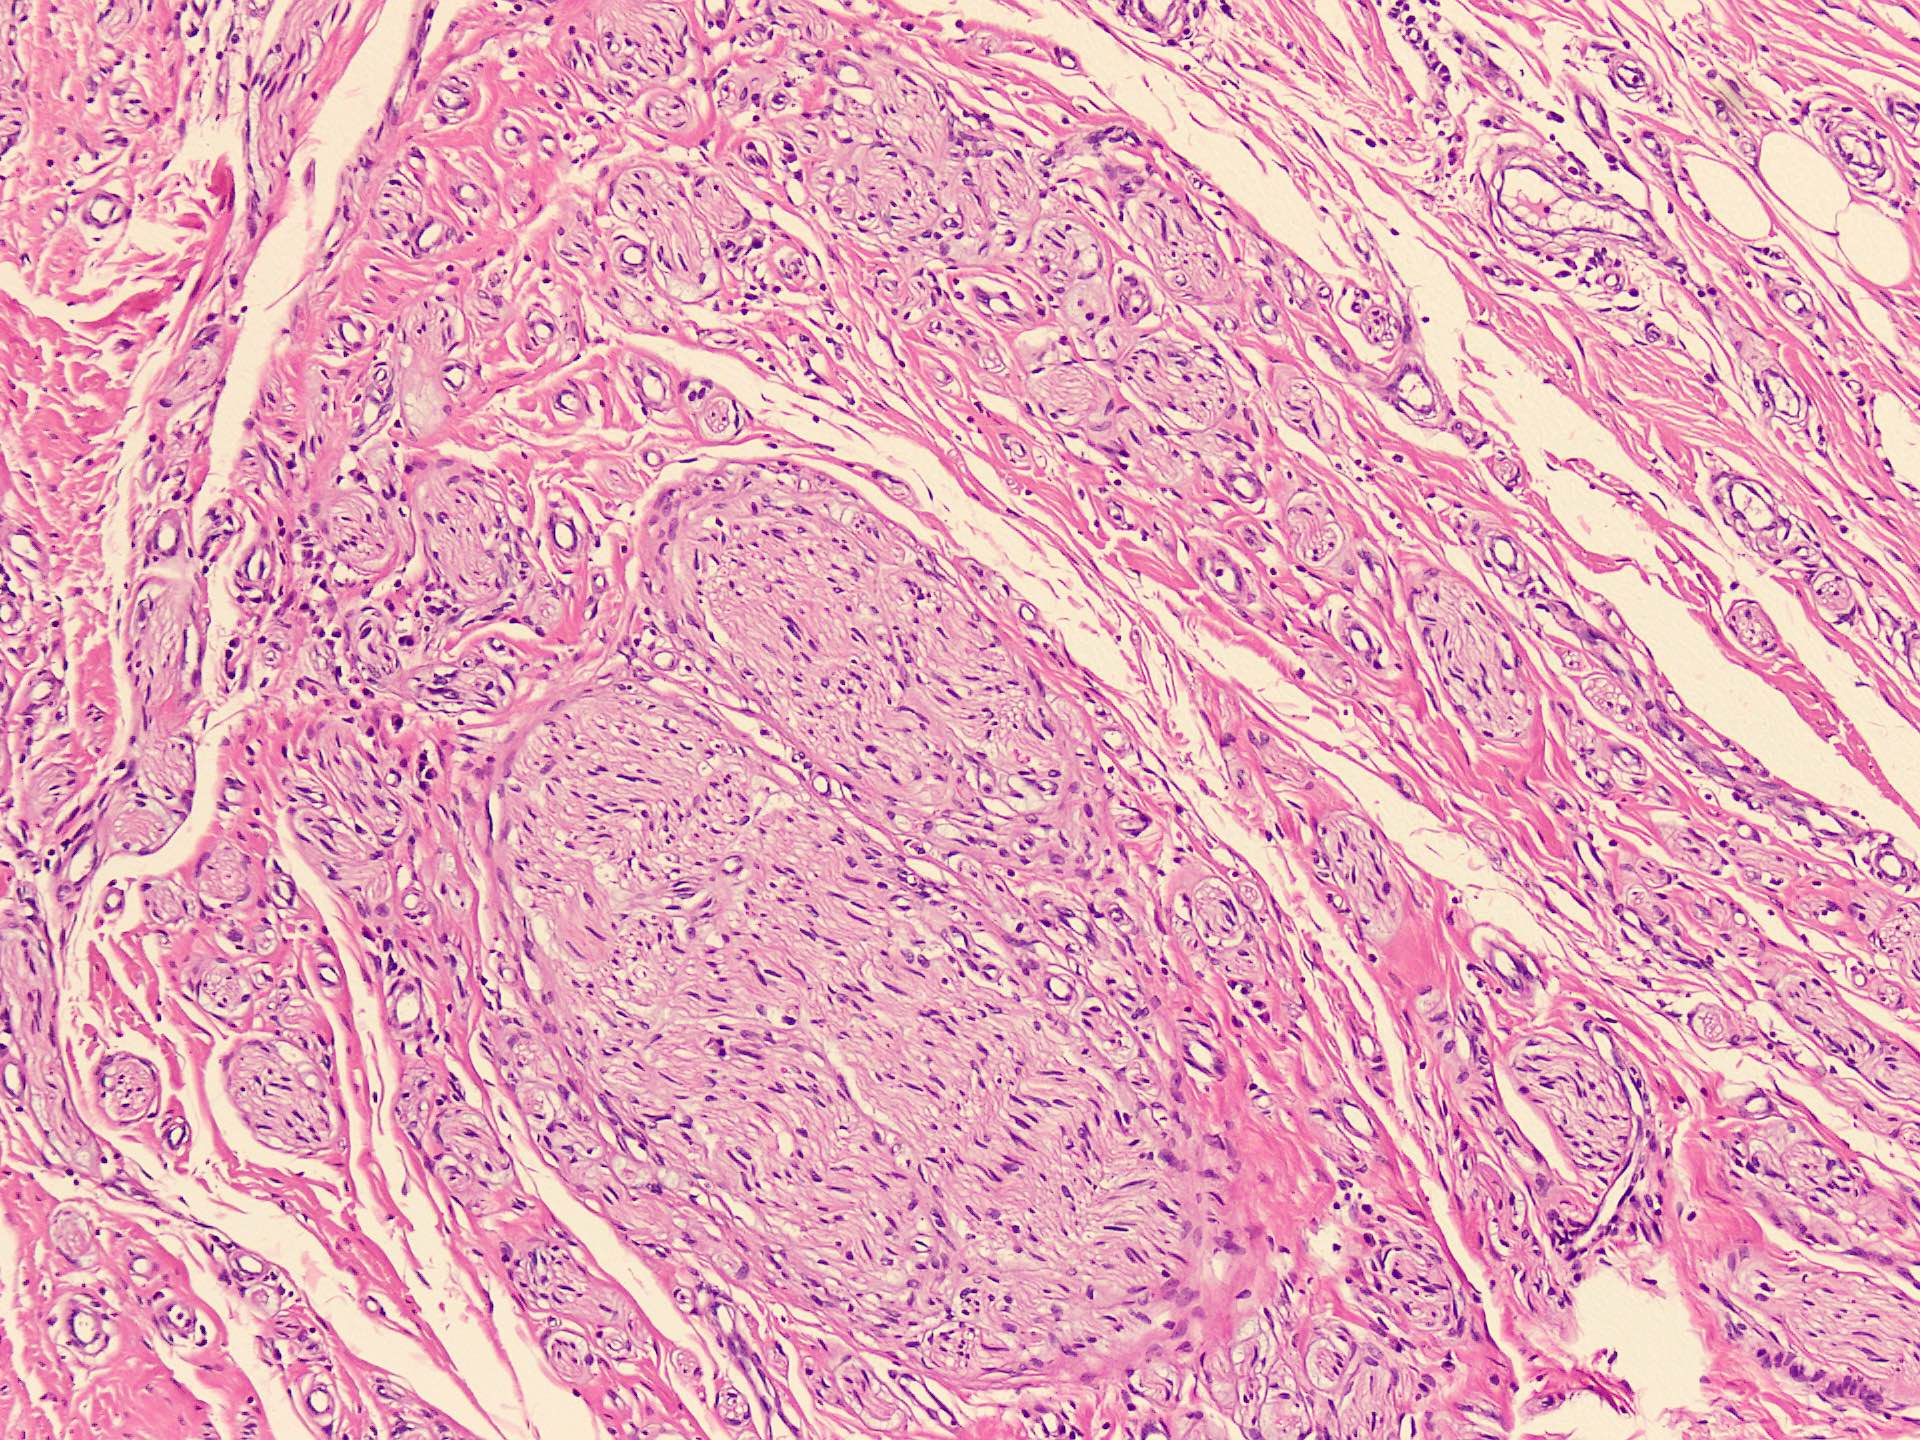

Microscopic (histologic) description

- Circumscribed, unencapsulated spindle cell proliferation arranged in short bundles comprised of axons, Schwann cells, endoneurial cells and perineurial cells (World J Clin Cases 2020;8:3821, Acta Biomed 2020;91:122, StatPearls: Neuroma [Accessed 21 September 2022])

- Peripheral palisading is not present (World J Clin Cases 2020;8:3821)

- Prominent scar tissue with dense collagen may be present (Acta Biomed 2020;91:122, StatPearls: Neuroma [Accessed 21 September 2022])

- Dystrophic calcifications are rarely present (Acta Biomed 2020;91:122)

Microscopic (histologic) images

- Microscopy: The sections examined show a circumscribed, unencapsulated lesion composed of variable sized, closely packed nerve bundle along with scar tissue in the background.

A patient presented with a painful nodule that developed after an amputation of the left first finger. On examination, the nodule is painful. Excision of the lesion is performed which shows the histology above. Which of the following is the most likely diagnosis?